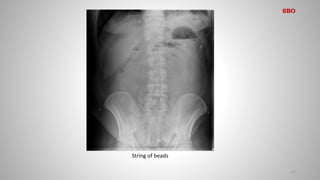

SBO

Obstruction (high-grade mechanical obstruction) may also present with

the following features:

• Gasless abdomen

• ‘String of beads’ sign: a line of gas bubbles trapped between the

valvulae conniventes within almost completely fluid-filled and very

dilated small bowel

String of beads